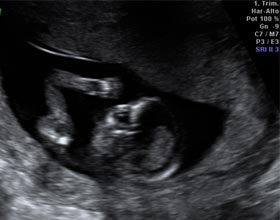

Se diferencian perfectamente la cabeza, los brazos, las piernas y el torso en la ecografía de la semana 13. Se aprecian las órbitas de los ojos y la boca abriéndose y cerrándose. Puede visualizarse al bebé chupándose el dedo. Es normal verle dando patadas y moviendo los brazos.

Aún se puede medir el pliegue nucal de tu bebé

En esta semana de gestación todavía se puede realizar la medición de la translucencia nucal como parte del test de cribado combinado. Algunos ginecólogos realizan solo la medición del pliegue o translucencia nucal como cribado de aneuploidías, en lugar del cribado combinado que utiliza datos ecográficos y analítico.